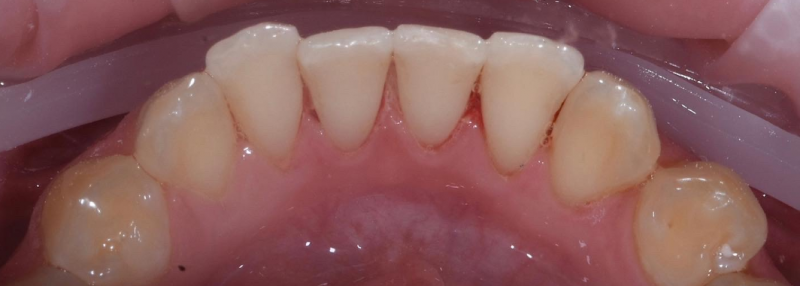

На странице представлено портфолио стоматологий Санкт-Петербурга с работами до и после профессиональной чистки зубов. В нашем портфолио собраны разные клинические случаи: от удаления незначительного налета до снятия массивного поддесневого камня. Здесь вы можете увидеть, как возвращается естественный цвет и внешний вид зубов после процедуры. Изучите результаты до и после чистки зубов, чтобы увидеть реальный эффект и выбрать клинику в Санкт-Петербурге, где профессиональная гигиена поможет вернуть зубам здоровый вид.

Профгигиена